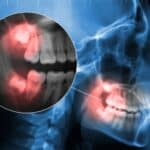

Η κροταφογναθική διάρθρωση (ΚΓΔ) είναι μία από τις πιο σύνθετες και ζωτικές αρθρώσεις του ανθρώπινου σώματος. Βρίσκεται εκατέρωθεν του κρανίου, μπροστά από τα αυτιά, και επιτρέπει τις κινήσεις της κάτω γνάθου κατά την ομιλία, τη μάσηση, την κατάποση και την έκφραση. Όταν η λειτουργία της διαταραχθεί σοβαρά και μη αναστρέψιμα, η ολική αρθροπλαστική κροταφογναθικής άρθρωσης αποτελεί την τελική, εξειδικευμένη λύση, προσφέροντας σημαντική ανακούφιση και αποκατάσταση της κινητικότητας.

Η ολική αρθροπλαστική κροταφογναθικής άρθρωσης είναι μια χειρουργική επέμβαση αντικατάστασης της άρθρωσης με τεχνητά εμφυτεύματα τιτανίου ή βιοσυμβατών υλικών, που μιμούνται την φυσιολογική λειτουργία της άρθρωσης.

Πρόκειται για μια τεχνολογικά εξελιγμένη επέμβαση, παρόμοια με την αρθροπλαστική ισχίου ή γόνατος, που εφαρμόζεται σε επιλεγμένες περιπτώσεις σοβαρής παθολογίας, όπου άλλες θεραπευτικές επιλογές έχουν αποτύχει.